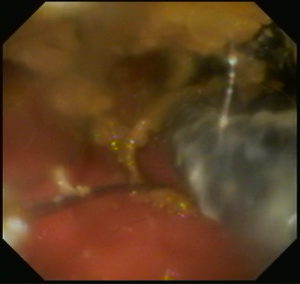

まず、食道内に1本太めのヘアゴムらしきものを認めたため、W字鉗子にて摘出しました。

その後、胃の中まで内視鏡を進め胃内を確認したところ、幽門部にひも状の異物の塊がはまっているのを発見しました。